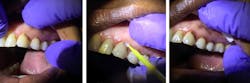

Silver diamine fluoride is applied to root decay (click to enlarge).